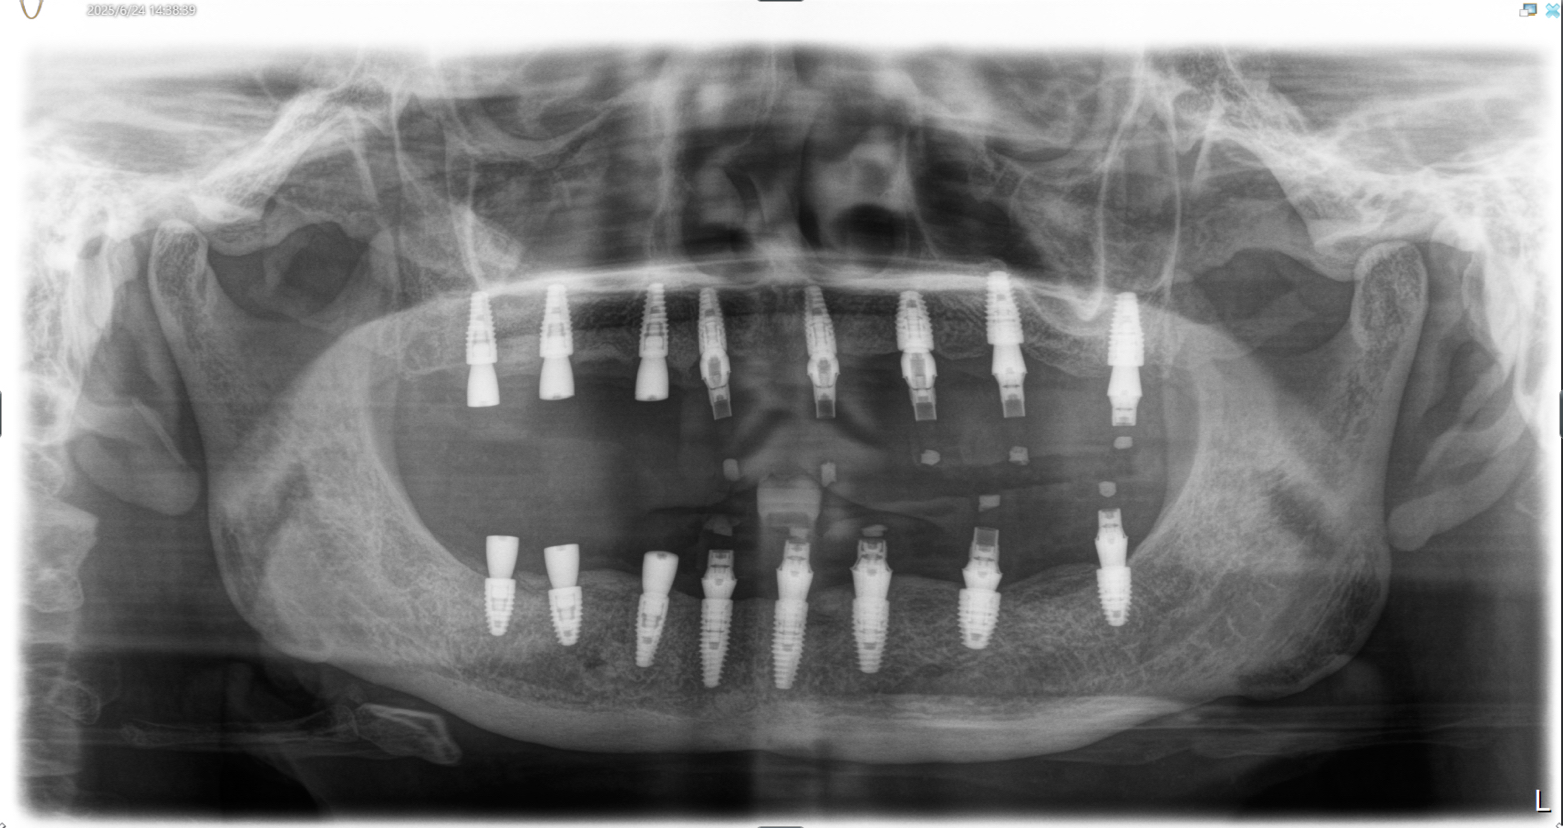

该患者就是因牙周病导致牙齿松动脱落,我们通过在全口牙槽骨上植入16颗种植体,然后在种植体上安装连桥牙冠,从而恢复半口牙齿的咀嚼功能和美观。相对于传统的种植修复方式缺一颗种一颗。4-8颗种植体的种植手术创伤相对较小,大大的减少了患者的疼痛感。